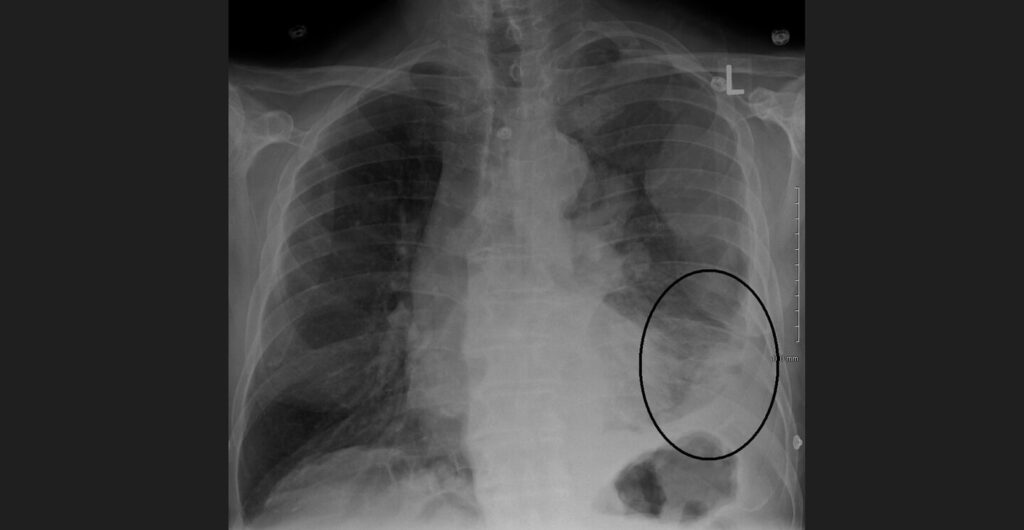

Mesotelioma Pleural: Advogado Explica Direito das Vítimas

Entenda o que é o mesotelioma pleural, seus sintomas, tratamentos e o direito à indenização por exposição ao amianto. Consulte um advogado especialista.